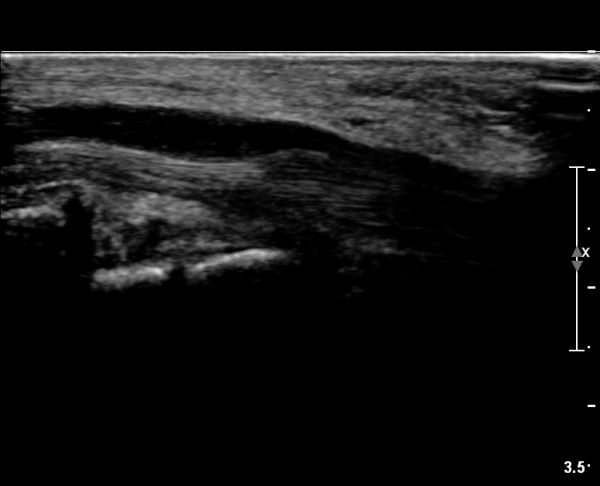

ÃÊÀ½ÆÄ ¼Ò°ß :  ¼Õ¸ñ±ÙÀ§ºÎ Ⱦ´Ü¸é°Ë»ç¿¡¼­ ¼Õ¸ñ±¼±Ù°Ç(FCR)°ú Ç¥Ãþ ¼Õ°¡¶ô ±ÁÈû±Ù(FDS) »çÀÌ¿¡

Á¤Á߽ŰæÀÌ Á¤»óÀûÀÎ ¾ç»óÀ¸·Î º¸ÀÓ(»çÁø 1).

Å½ÃËÀÚ¸¦ ¸»´ÜÀ¸·Î À̵¿ÇÏÀÚ  Á¤Áß½Å굥 ¿äÃø ÀϺΰ¡ Àú¿¡ÄÚ Á¾±«·Î °üÂûµÊ(»çÁø 2).

ÀÌ·± ¸ð½ÀÀº ¼Õ¸ñÀÇ ¿ù»ó°ñ ºÎÀ§(»çÁø 3, 4)¸¦ Áö³ª ¼ö±Ù°ü ±ÙÀ§ºÎ ±îÁö À̾îÁü(»çÁø 5).